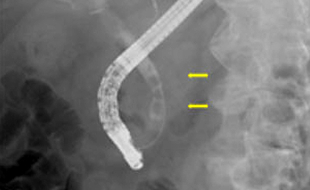

• 内視鏡的逆行性胆膵管造影検査

胆管炎の原因になる胆管結石を内視鏡で治療することができます。

• 内視鏡的逆行性胆膵管造影検査(胆管結石の治療や胆膵腫瘍の精密検査)